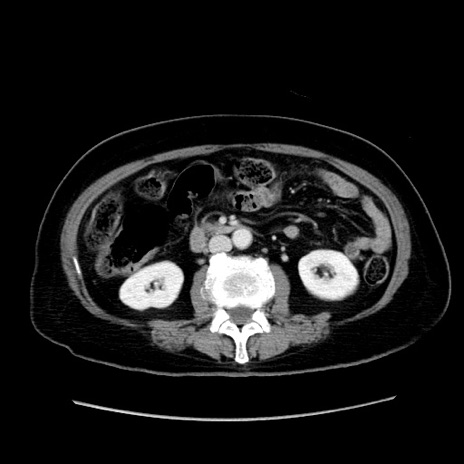

症例

冠状断像

【症例】80歳代女性

【主訴】下腹部痛

【現病歴】約8時間前より下腹部痛の出現あり、救急外来受診。

【既往歴】両側付属器切除

【身体所見】意識清明、下腹部正中に手術痕あり、その部位に一致して圧痛と反跳痛あり。腸蠕動音は亢進。

【データ】WBC 9300、CRP 0.15